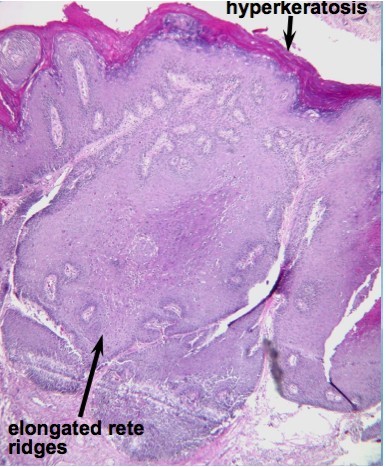

Lichen sclerosis: inflammatory disorder of vulva, seen mostly in post-menopausal women. Associated with autoimmune disorders (vitiligo, pernicious anemia, thyroiditis). See whitish plaques, atrophy, parchment-like skin.

Histology: hyperkeratosis of vulvar skin, loss of rete ridges, devleopment of acellular homogenous zone of superficial dermis